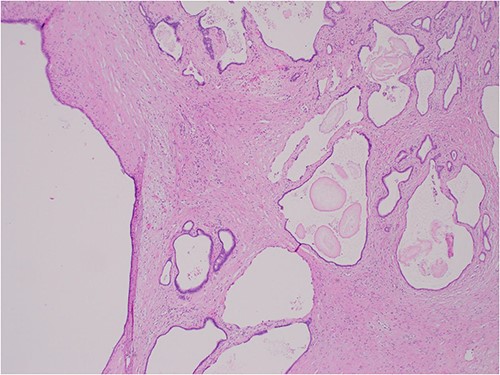

The histologic examination revealed numerous large, medium and small cysts separated by prominent stromal areas of fibrosis. These areas contained luminal eosinophilic concretions (Fig. 3). No ovarian-type parenchyma was found to suggest IPMN. The cyst formation maintained the outline of the native lobules, with some withered central islets appreciated. No papillary architecture was observed, and no epithelial dysplasia or invasive carcinoma was present. Epithelium lining the cysts was attenuated in some areas, and cuboidal in others. Where the epithelium was recognizably cuboidal, there was scattered acinar differentiation noted, characterized by apical cytoplasmic granules positive on periodic acid-Schiff-diastase (PASD) staining (Fig. 4). Acinar differentiation did not therefore have to be confirmed with further immunohistochemistry.

Hematoxylin and Eosin (H&E) × 40 showing benign cysts and luminal eosinophilic concretions.